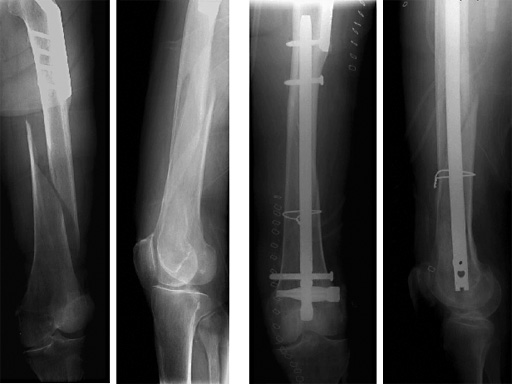

Female, 88 years

Distal Femoral Nail with Spiral Blade

In the past years, retrograde femoral nailing has proven to be safe and reliable. The Distal Femoral Nail is becoming increasingly popular and is especially suitable for obese (or pregnant) patients and in osteoporotic metaphyseal bone.

Indications include extra-articular metaphyseal distal femoral fractures (32-A1 to C3) and supracondylar fractures and simple articular fractures (33-A1 to A3 and 33-C1 to C3.1).

The Spiral Blade enables significantly more stable distal interlocking than with conventional locking bolts due to the large load-bearing surface. It reduces cancellous bone compaction and lowers the risk of nail protrusion into the knee joint. The nail diameters are 9.0 and 10.0 mm for solid nails and 12.0 mm for cannulated nails.